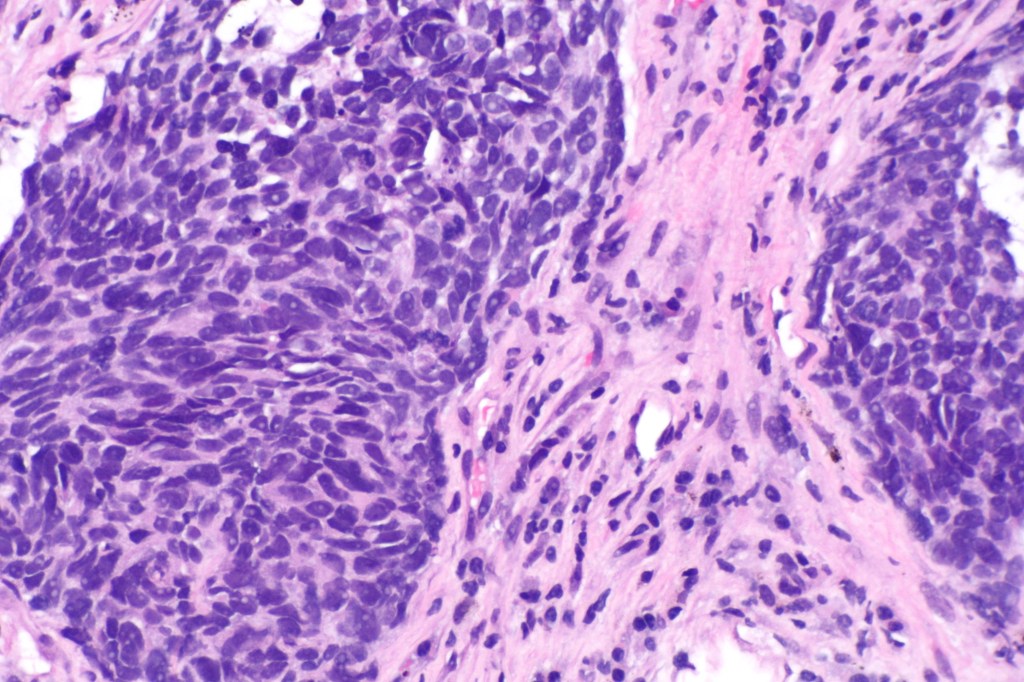

[2] Image retrieved from: https://upload.wikimedia.org/wikipedia/commons/9/94/Non-small_cell_lung_carcinoma_–_high_mag.jpg